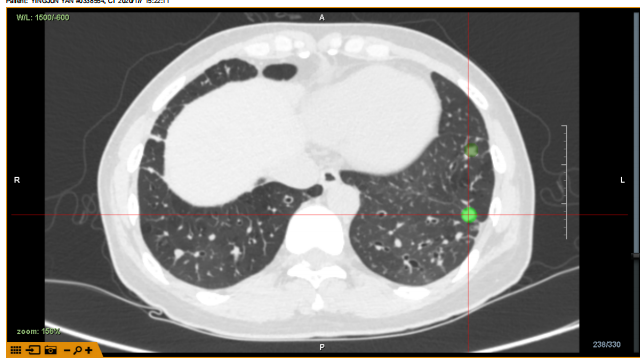

病例2:病灶位于LB9,大小约9mm,隧道路径约34mm,POE 点位于RB9亚亚段。

病例2

X光与超声确认抵达病灶